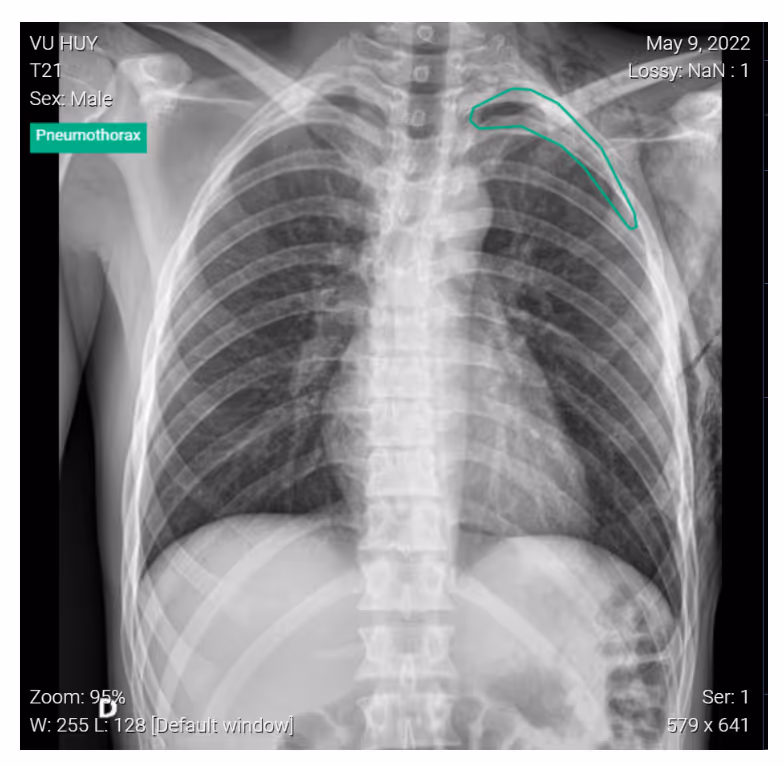

To prevent quick progression of small pneumothorax to a large-size pneumothorax, chest x-rays must be repeated within 3-6 hours after admission for patients on observation. Spontaneous hemopneumothorax must be considered during this period. Imaging evaluation should be done within 12-48 hours after discharge. Admission observation is recommended for patients without reliable follow-ups to prevent the condition from worsening.

DrAid for Pneumothorax helps to compare side-by-side images for follow-up in pneumothorax patients. This aided reading allows doctors to create a suitable treatment plan for the patient.Interested in deploying DrAid at your health facility?